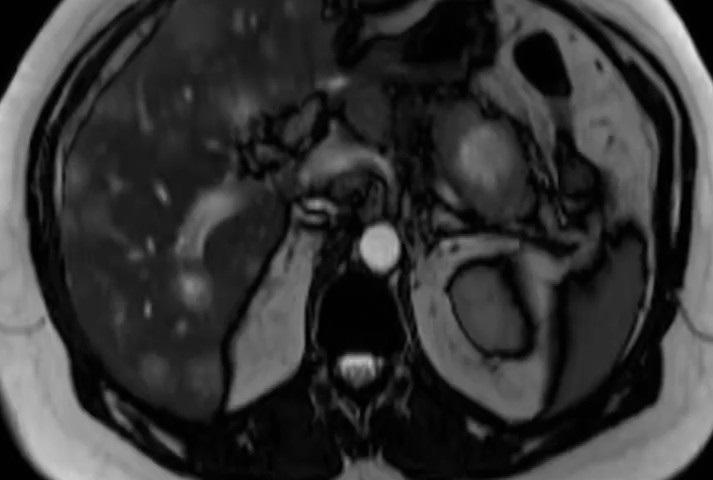

وأضاف: "هذا كان عند مريض جاءني قبل اسبوعين وتبين ان فحص الحمل كان ايجابيا نتيجة افرازه من ورم في البنكرياس منتشر للكبد. بعدما اخذت عينات من ورم الكبد تحت الاشعة المقطعية وفحصه تحت المجهر تبين ان الورم يفرز هرمون الحمل. وهذا يمثل حالة نادرة من الاورام ولها علاجها الخاص".

وأردف: "الفيديو يظهر عملية اخذ الخزعة من الكبد والفحص النسيجي الذي اكتشف الورم".